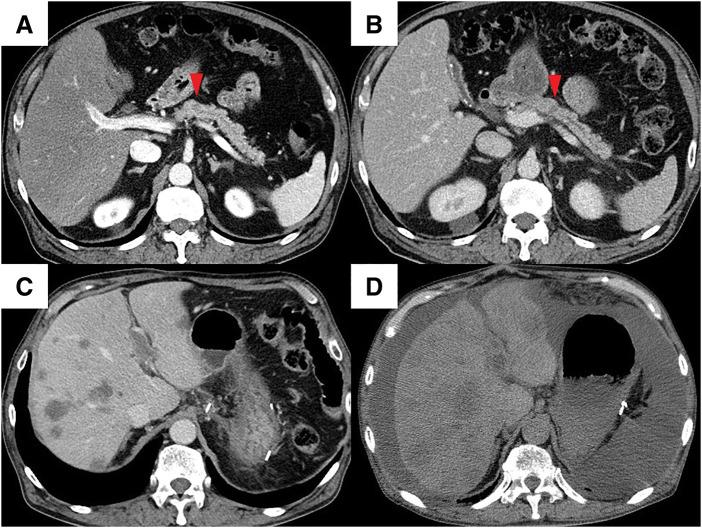

病例1中,一名49岁女性,胰体部有一个12毫米的肿瘤(cT1N0M0,c期IA,国际癌症控制联盟[UICC]第8版),接受了两个疗程的新辅助GS治疗,随后进行了开放性胰体尾切除术。病理检查显示无残留癌,患者被诊断为病理完全缓解(pCR),术后31个月无复发。然而,病例2中,一名74岁男性,胰体部也有一个12毫米的肿瘤(cT1N0M0,c期IA,UICC第8版),同样接受了两个疗程的新辅助GS治疗,然后进行了腹腔镜胰体尾切除术。病理检查显示为浸润性胰腺导管腺癌,肿瘤大小为20毫米。肿瘤侵犯脾静脉腔和腹膜后组织(ypT1N0M0,yp期IA,UICC第8版)。开始使用S-1进行辅助化疗,但术后4个月,血清CA19-9水平显著升高,出现多处肝转移和门静脉肿瘤血栓。开始使用吉西他滨联合白蛋白结合型紫杉醇(GnP)治疗,然而,肿瘤进展迅速。患者术后6个月死亡。